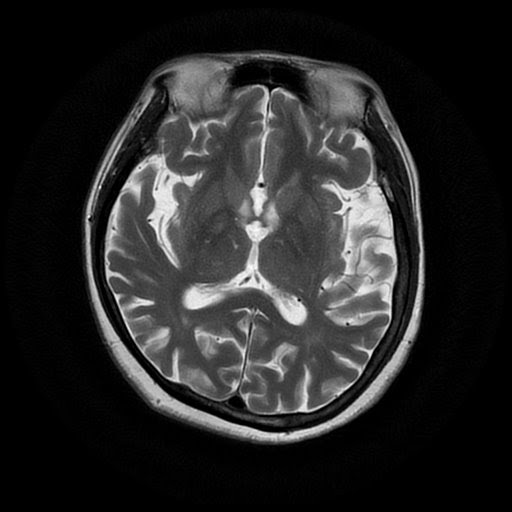

Alzheimer's X Ray . Doctors frequently request a ct or mri scan of the brain when they are examining a patient with suspected dementia. Medial temporal lobe atrophy on mri differentiates alzheimer’s disease from dementia with lewy. A head ct can show shrinkage of brain. Medial temporal lobe atrophy on mri differentiates alzheimer’s disease from dementia with lewy bodies and vascular cognitive impairment: To rule out other possible causes of your symptoms and look for possible signs of damage caused by alzheimer's disease, your specialist may. Ct scans are the most common type of brain scan used in. Areas that are black and blue represent. The scans show a healthy brain, a brain with mild cognitive impairment and a brain with alzheimer's disease.

A head ct can show shrinkage of brain. Medial temporal lobe atrophy on mri differentiates alzheimer’s disease from dementia with lewy. Doctors frequently request a ct or mri scan of the brain when they are examining a patient with suspected dementia. Areas that are black and blue represent. To rule out other possible causes of your symptoms and look for possible signs of damage caused by alzheimer's disease, your specialist may. The scans show a healthy brain, a brain with mild cognitive impairment and a brain with alzheimer's disease. Medial temporal lobe atrophy on mri differentiates alzheimer’s disease from dementia with lewy bodies and vascular cognitive impairment: Ct scans are the most common type of brain scan used in.

Alzheimer's X Ray Areas that are black and blue represent. Medial temporal lobe atrophy on mri differentiates alzheimer’s disease from dementia with lewy bodies and vascular cognitive impairment: The scans show a healthy brain, a brain with mild cognitive impairment and a brain with alzheimer's disease. Medial temporal lobe atrophy on mri differentiates alzheimer’s disease from dementia with lewy. Doctors frequently request a ct or mri scan of the brain when they are examining a patient with suspected dementia. To rule out other possible causes of your symptoms and look for possible signs of damage caused by alzheimer's disease, your specialist may. A head ct can show shrinkage of brain. Areas that are black and blue represent. Ct scans are the most common type of brain scan used in.